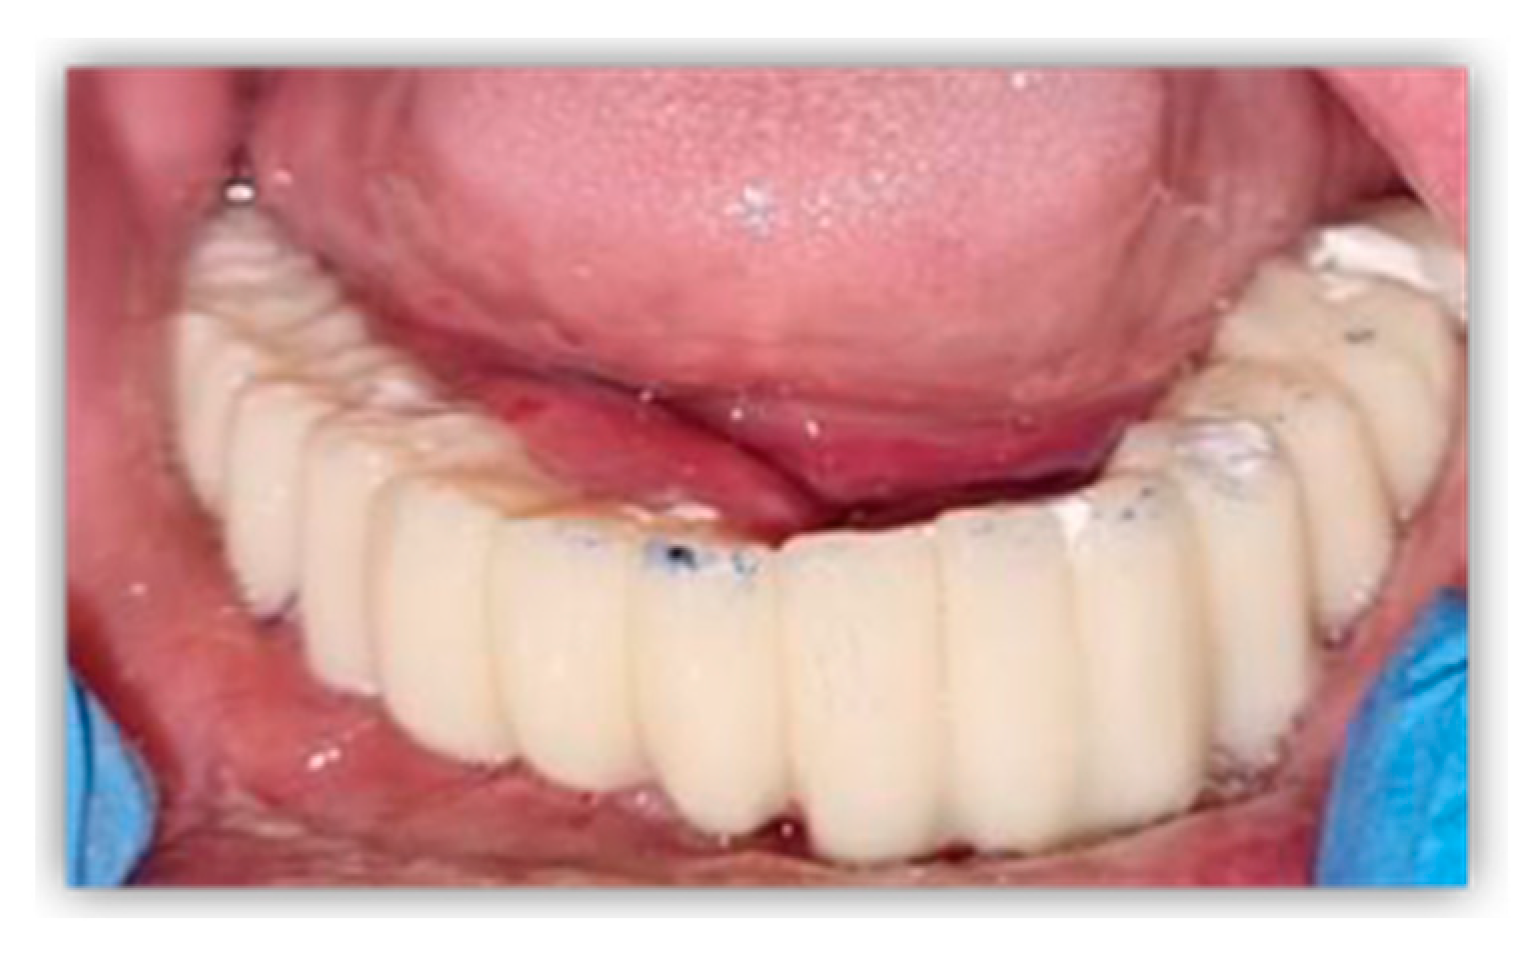

Immediately after surgery, a direct impression was recorded using open-tray and polyether impression material (Impregum, 3 M ESPE, St. Paul, MN, USA). Bite registration was performed using an occlusion rim, and the next morning, the patient received a milled polymethyl methacrylate (PMMA) interim denture, restoring their dental functions and facial aesthetic. Using screws, the provisional prosthetic restoration was fixed to the level of the remaining dental implants and mesh prosthetic connections (Figure 6).

Figure 6.

Intraoral aspect of milled PMMA interim denture.